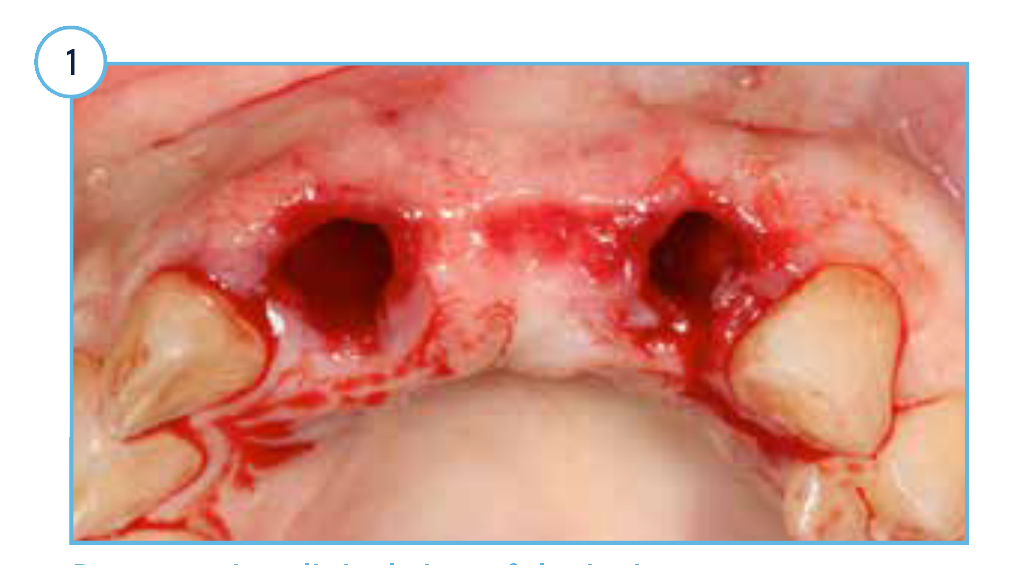

Preoperative clinical view of the incisor extraction sockets.

TSVT Implants (4.1 mm x 16 mm) with attached fixture mounts threaded into the prepared extraction sockets.